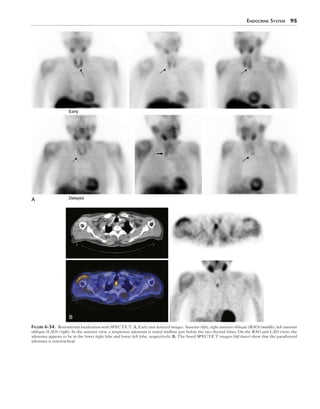

Single-photon emission computed tomography (SPECT),

but particularly SPECT with CT (SPECT/CT) can be con-

firmatory (Fig. 6-22).

Figure 6-22.  Substernal goiter with I-123 hybrid SPECT/CT. The I-123 thyroid scan is fused with the CT scan in selected transverse, sagittal, and

coronal views. This patient had a multinodular toxic goiter with substernal extension.